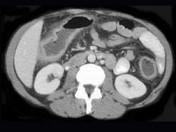

问题 女,40岁,腹痛、腹泻、脓血便、里急后重,结合图像,选择最可能诊断 ( )

选项 A.假膜性肠炎 B.结肠克罗恩病 C.结肠结核 D.慢性溃疡性肠炎 E.结肠淋巴瘤

答案 D